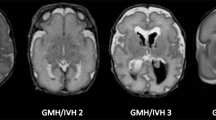

WM injury

All T1-W and T2-W sequences were analysed by two investigators (FTdB, paediatric neuroradiologist with more than 15 years of experience, LML, with more than 4 years’ experience) by consensus to assess WM injury. We categorised the WM injury into [41]:

-

Normal/mildly abnormal WM: normal appearing WM or homogeneous diffuse and excessive high signal intensity (DEHSI) as seen on T2-weighted images, or few (≤6) punctate white matter lesions (PWML)

-

Moderately abnormal WM: multiple (> 6) PWML and/or small localised cystic lesions and/or heterogeneous DEHSI

-

Severely abnormal WM: extensive or diffuse heterogeneous signal intensity changes and/or haemorrhagic or cystic lesions involving the periventricular and/or subcortical WM

Accordingly, 18 infants were classified as having normal/mildly, 51 infants moderately and 15 infants severely abnormal WM (Table 1)